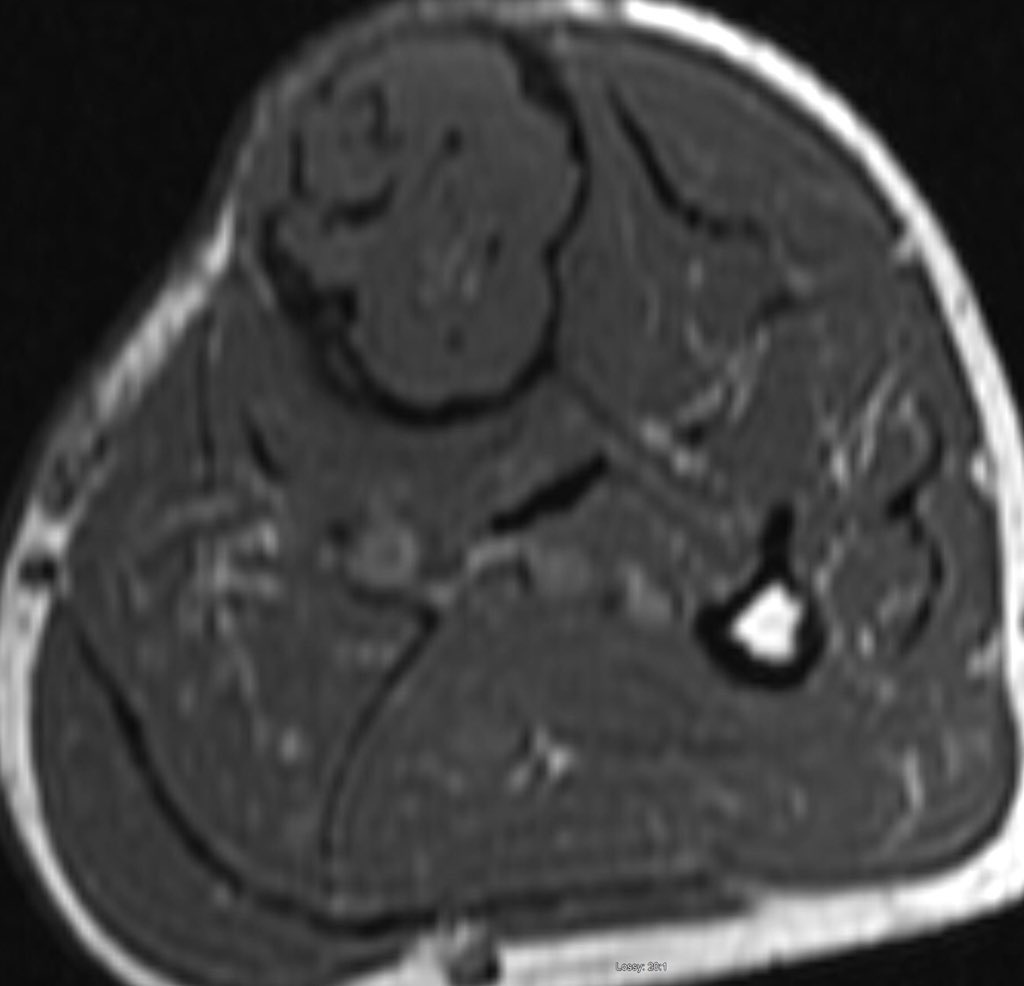

A single destructive lesion or multifocal tumour,may be identified, affecting cortex and often extending to the medulla,most commonly in the mid-tibial shaft.The lesion is typically eccentric and may cause mild bone expansion,endosteal scalloping and eventually destroy the cortex

AD typically appears multilocular and trabeculated, with intervening and surrounding sclerosis. A distinct periosteal reaction is unusual. An extra-osseous mass and pathological fracture may be seen

MRI is mandatory for accurate local staging (intramedullary extent, multifocal tibial and fibular disease and extra-osseous extension) and surgical planning. AD is typically isointense / mildly hyperintense to muscle on T1 weighted images

similar to fat on fast spin-echo T2 and hyperintense on inversion recovery and fluid-sensitive fat saturated sequences. The tumour enhances intensely and homogeneously.